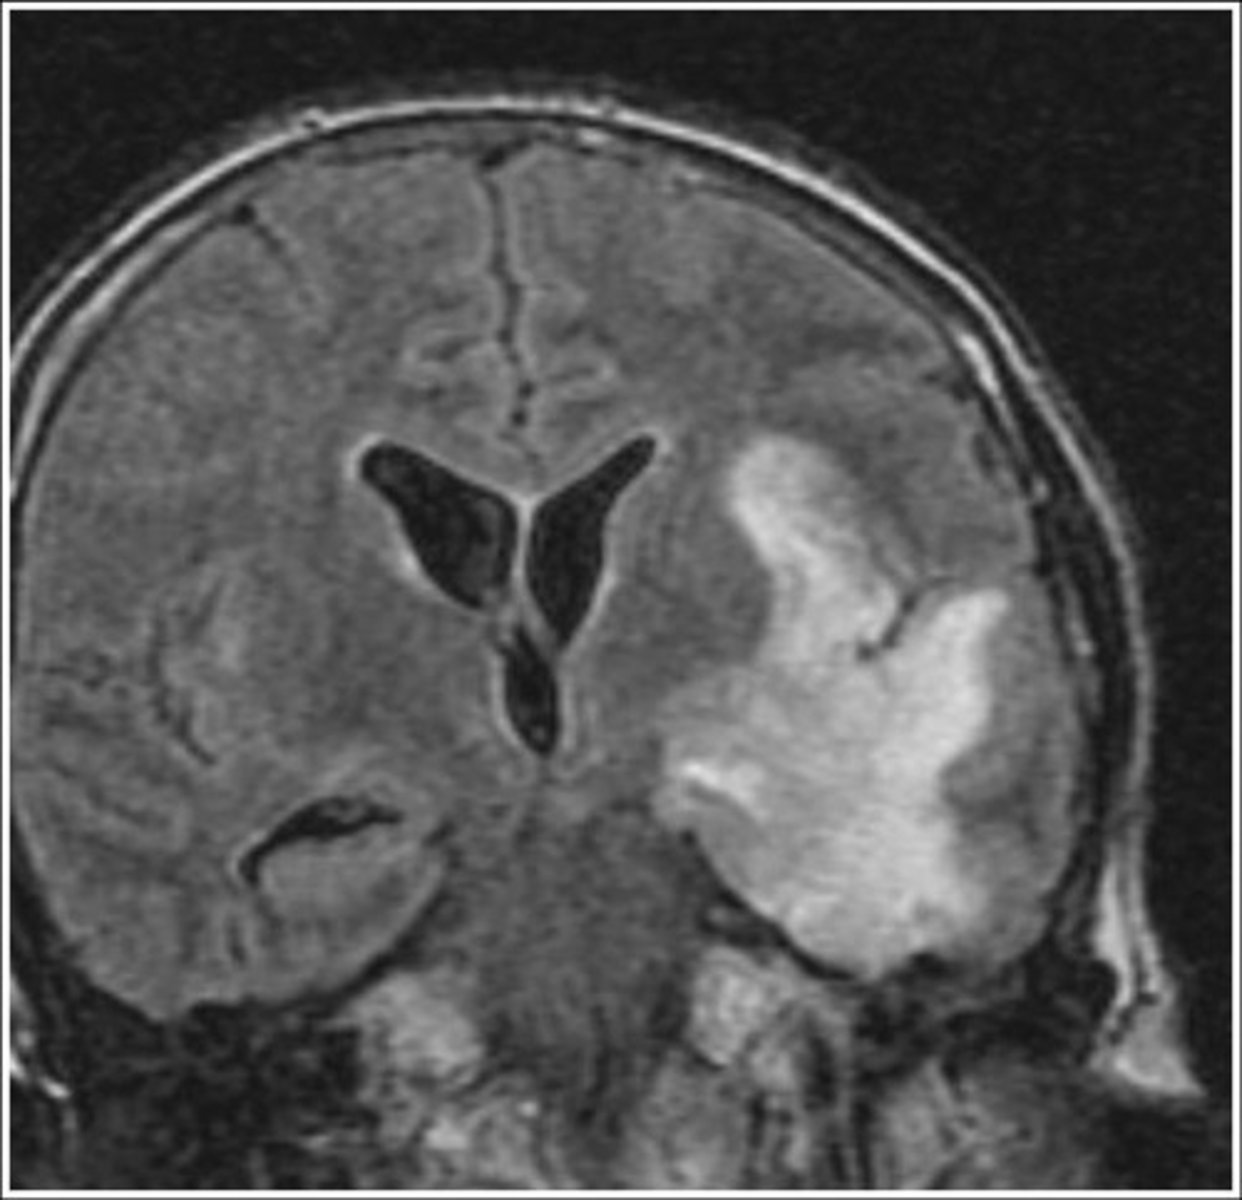

What are complications of mumps?

2)meningitis (inflammation of meninges covering brain)

3)encephalitis (inflammation of brain)

encephalitis

inflammation of the brain